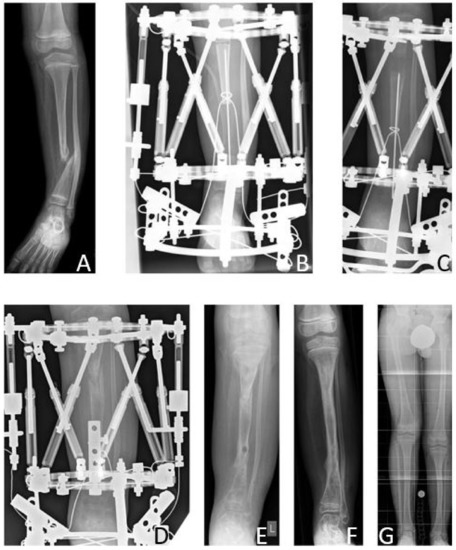

According to the modified Johnston criteria, there was one result grade 1, two grade 2, and three grade 3 (Figure 6).

Figure 6. Results Group A. Seven-year-old male patient presenting CPT Paley type 3 (A). Bone transport was performed over a total distance of 50 mm (B,C). After bone docking (D) the external fixator was applied for another three months. After removal of the fixator (E), full bone consolidation was observed after 10 months (F). Five years after reconstruction, at the age of 13 years, the patient showed a remaining LLD of 2.8 cm (G).